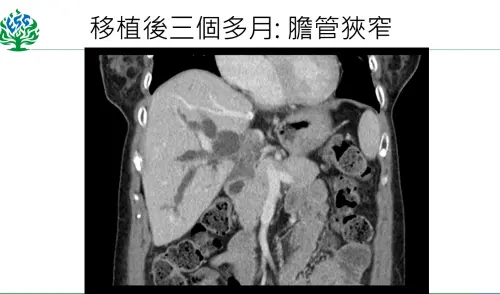

▲個案移植後3個月出現併發感染與膽管狹窄,經置放膽管支架後,順利恢復。(圖/馬偕醫院提供) 33歲兒捐肝救母 出血量近萬

米德莉在全肝臟切除下,而肝硬化的肝臟「表面如同苦瓜」。接受兒子恰德60%的肝臟,手術耗時12小時,出血量達9950c.c.。但移植後3個月,米德莉追蹤肝功能卻不太對勁,數值愈來愈高,發現併發感染與膽管狹窄,移植團隊會診消化科系,以內視鏡置放膽管支架後,目前則順利恢復,即將於3月26日回到帛琉。